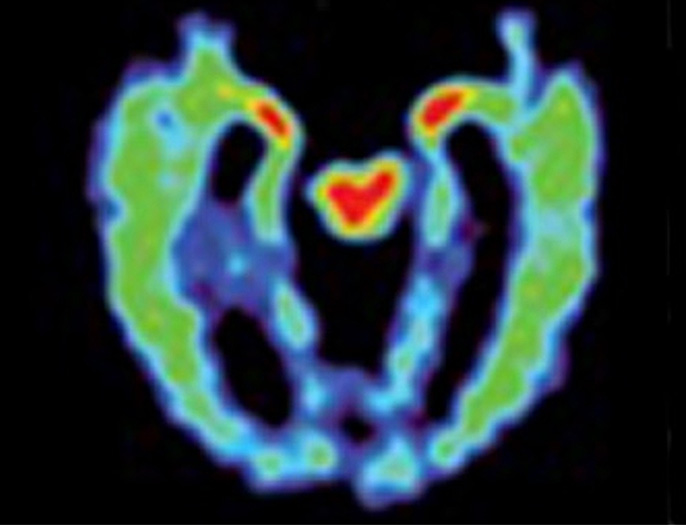

“The distribution pattern of the abnormal brain proteins, primarily tau, observed in these PET scans, presents a ‘fingerprint’ characteristic of CTE,” said Dr. Jorge Barrio, senior author of the study and a professor of molecular and medical pharmacology at the David Geffen School of Medicine at UCLA.

The PET scans revealed that the imaging patterns of the retired football players showed tau deposit patterns consistent with those that have been observed in autopsy studies of people with CTE.

Compared with healthy people and those with Alzheimer’s, the former athletes had higher levels of FDDNP in the amygdala and subcortical regions of the brain, which are areas that control learning, memory, behavior, emotions, and other mental and physical functions.

People with Alzheimer’s, on the other hand, had higher levels of FDDNP in areas of the cerebral cortex that control memory, thinking, attention and other cognitive abilities. And the athletes who had experienced more concussions also had higher FDDNP levels.